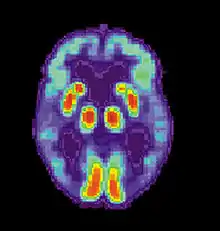

A follow-up to the previous research was conducted by Daniel L. Schacter and colleagues. Similar to the study by Henry L. Roediger and Kathleen McDermott, subjects were read a list of associated words before they went into the PET scanner. During the first scan, subjects would make recognition judgments to determine what were the previous presented words.[2] During the second scan, subjects had to make judgments about words that were not presented. For example: bed, rest, dream, tired, and awake would be in the list but not the word "sleep". As with the study by Henry L. Roediger and Kathleen McDermott, subjects claimed to remember similar amounts of non-presented words as they did the words that were actually presented.[2] The researchers noted that brain activity during the true and false recognition tasks were very similar. Monitoring the blood flow in the brain revealed there were in the left medial temporal lobe for both veridical and illusory recognition.[17]

That is not to say that there were not differences. While monitoring blood flow in the brain during false recognition, a part of the frontal lobe that is thought to be a key monitor of memories actually showed greater activity when presented with a false recognition than with a true one.[2] There seemed to be some discrepancy as subjects attempted to scrutinize the out-placed words, but were overcome by powerful memory illusion.[2] This study demonstrates the ability of technology to help researchers understand to a greater extent the power of false memories.